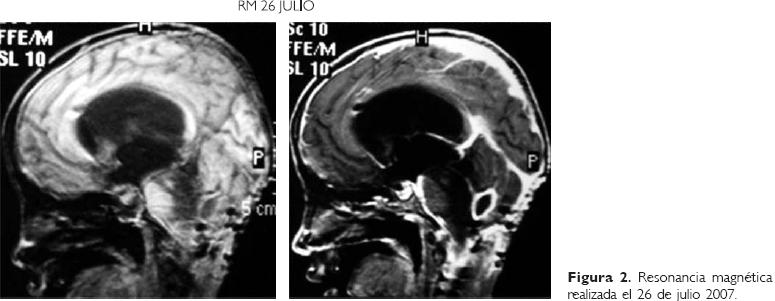

No se cuenta con estudio inicial de RM; en el estudio realizado el 26 de julio (Fig. 2), podemos observar, en la secuencia eco de gradiente (también llamada secuencia hemo), en el lecho quirúrgico, un remanente de hemosiderina con una colección adyacente. Llama la atención que persistía con la dilatación importante de los ventrículos, discretamente asimétrica, observando en la región parietooccipital derecha, una zona también con restos de hemosiderina. En el resto del estudio, en fase simple, observamos una imagen heterogénea en lo que fue la zona del tumor, observando una hiperintensidad periférica, que correlaciona con una zona de sangrado en fase tardía, y la imagen sagital T1 simple, mostró zona heterointensa que, con la administración de gadolinio, tuvo un realce intenso de su periferia, con una zona hipointensa en su interior. Cabe recalcar que se observó un realce de las meninges de forma generalizada; en toda la base del cráneo, por delante del tallo cerebral, se apreció una imagen que se continuaba hacia el conducto raquídeo, por lo que se realizó una imagen de extensión de toda la columna (imagen T1 sagital [Fig. 3]), en donde normalmente el LCR que rodea la médula es hipointenso, se apreciaba la médula, la zona del lecho quirúrgico, con hiperintensidad que correspondía a un realce meníngeo intenso, que rodeaba prácticamente a toda la médula.

Se concluye que se trató de un astrocitoma de alto grado, probablemente anaplásico, o un glioblastoma multiforme, con una imagen de neuroinfección; probable absceso en el lecho quirúrgico; y a descartar extensión, ya sea del tumor o del proceso infeccioso al resto del conducto raquídeo (Figs. 1, 2 y 3).